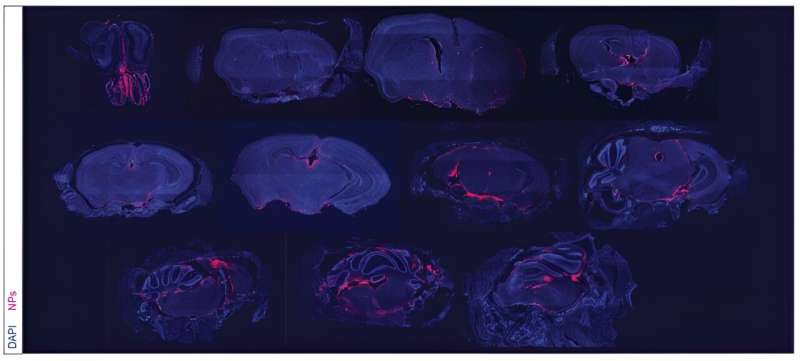

Representative distribution of 90 nm Cy5-NP throughout representative coronal sections of the head 6 h after i.c.m delivery (n=5, scale bar = 700 µm). Credit: Science Translational Medicine (2023). DOI: 10.1126/scitranslmed.adi1617

The nanoparticle treatment is injected intrathecally—that is, it's delivered directly between the leptomeninges protecting the CSF. Over a period of weeks, the researchers detected the presence of the nanoparticles in the CSF for as long as 21 days after a single dosing.